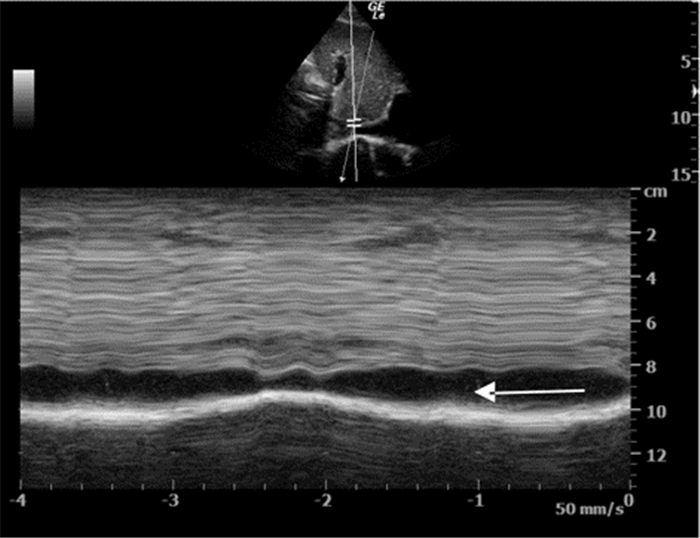

3.4.3 心肺复苏中超声诊断步骤及流程在心肺复苏中,为了避免超声检查对胸外按压的干扰,在心脏按压过程中实施心脏扫描,剑突下四腔心脏切面是最为理想的视窗。首先心脏超声可探及心脏运动(图 37),研究表明心脏骤停的患者被超声确认为心肌运动缺失的心搏停止时,其生存的希望极其渺茫。其次,超声检查还可以帮助寻找导致心脏骤停的可逆性病因。

| 图 37 M超判断心肌运动缺失情况(该图片由华中科技大学同济医学院附属协和医院重症医学科采集) |